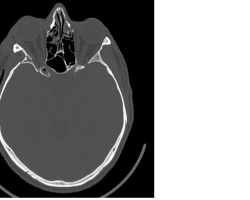

- TDM sans injection en coupes axiales, coronale et sagittale

Fracture du plancher orbitaire, du toit de l’orbite, de la paroi temporale. - Photos